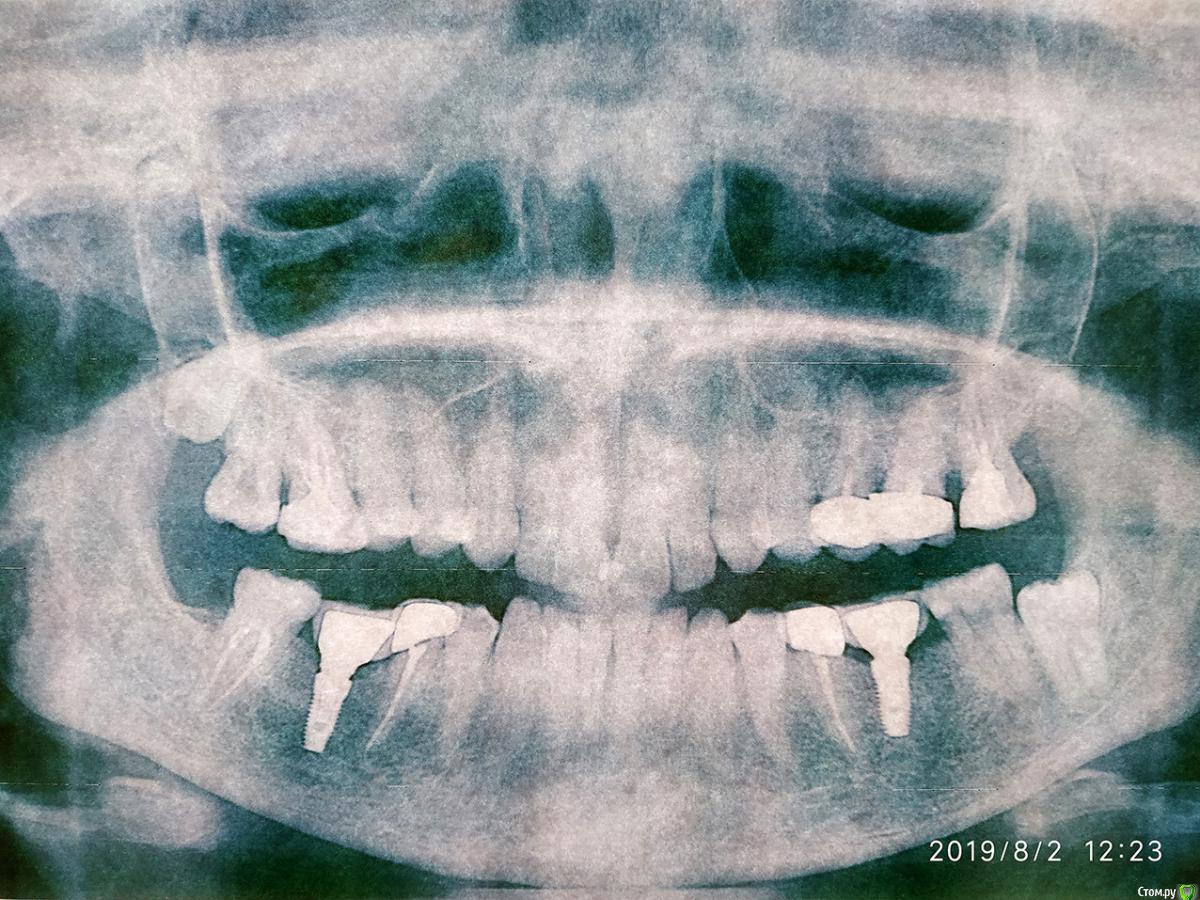

arinasmirn74@gmail.com Опубликовано 2 августа, 2019 Автор Поделиться Опубликовано 2 августа, 2019 (изменено) Ситуация до имплантации и после. Второй снимок в Пикассо фиговый, попробую переделать, но может быть что-то и понятно. Изменено 2 августа, 2019 пользователем arinasmirn74@gmail.com Ссылка на комментарий

arinasmirn74@gmail.com Опубликовано 1 августа, 2019 Поделиться Опубликовано 1 августа, 2019 Добрый день! Только что закончилась процедура протезирования - поставили коронки на две нижние шестерки и две пятерки (пятерки не импланты, свои).Справа нижней шестерки не было очень давно, антагонист выдвинулся, врач пришлифовал его в пределах эмали на этапе снятия слепков. Сегодня добивались комфортного прикуса, и вроде бы в статике и при небольших движениях все идеально подогнали, но, придя домой, я поняла, что имплант справа ниже остального ряда, а антагонист - выше, таким образом происходит вклинение антагониста в нижний зубной ряд, при активном жевании, движении по вектору зубного ряда верхний антагонист шестерки оказывается заклиненым между нижними 5 и 7 при смыкании с имплантом.Вот не знаю теперь, что делать.Понимаю, что врач решал проблему как мог: более глубокая пришлифовка - решение не очень (зуб - одна большая пломба с бессимптомной кистой), а сошлифовывать, обтачивать и убирать под коронку верхний антагонист с возвращением в общий зубной ряд нецелесообразно потому, что верхний антагонист имеет бессимптомную кисту и может в любой момент пойти под удаление. Что делать? Пытаться привыкнуть к зарубанию зуб о зуб? Удалять верхний антагонист и переделывать коронку нижней шестерки? Рискнуть и выровнять оба зуба (антагонист сточить по уровню, нижний переделать)?Можно ли переделать коронку на импланте через год-три-пять?ОПТГ завтра попробую сделать. Ссылка на комментарий